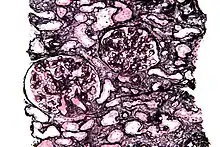

Micrograph of a kidney biopsy stained with a Jones stain.

Jones' stain, also Jones stain, is a methenamine silver-Periodic acid-Schiff stain used in pathology.[1] It is also referred to as methenamine PAS which is commonly abbreviated MPAS.

It stains for basement membrane and is widely used in the investigation of medical kidney diseases.

The Jones stain demonstrates the spiked GBM, caused by subepithelial deposits, seen in membranous nephropathy.